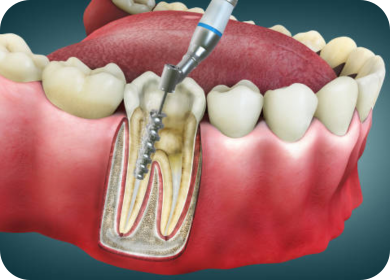

Our expert endodontic care focuses on saving infected or damaged teeth through pain-free root canal treatment. By cleaning and sealing the tooth from within, we eliminate infection, relieve discomfort, and restore full function—allowing you to keep your natural teeth for years to come.